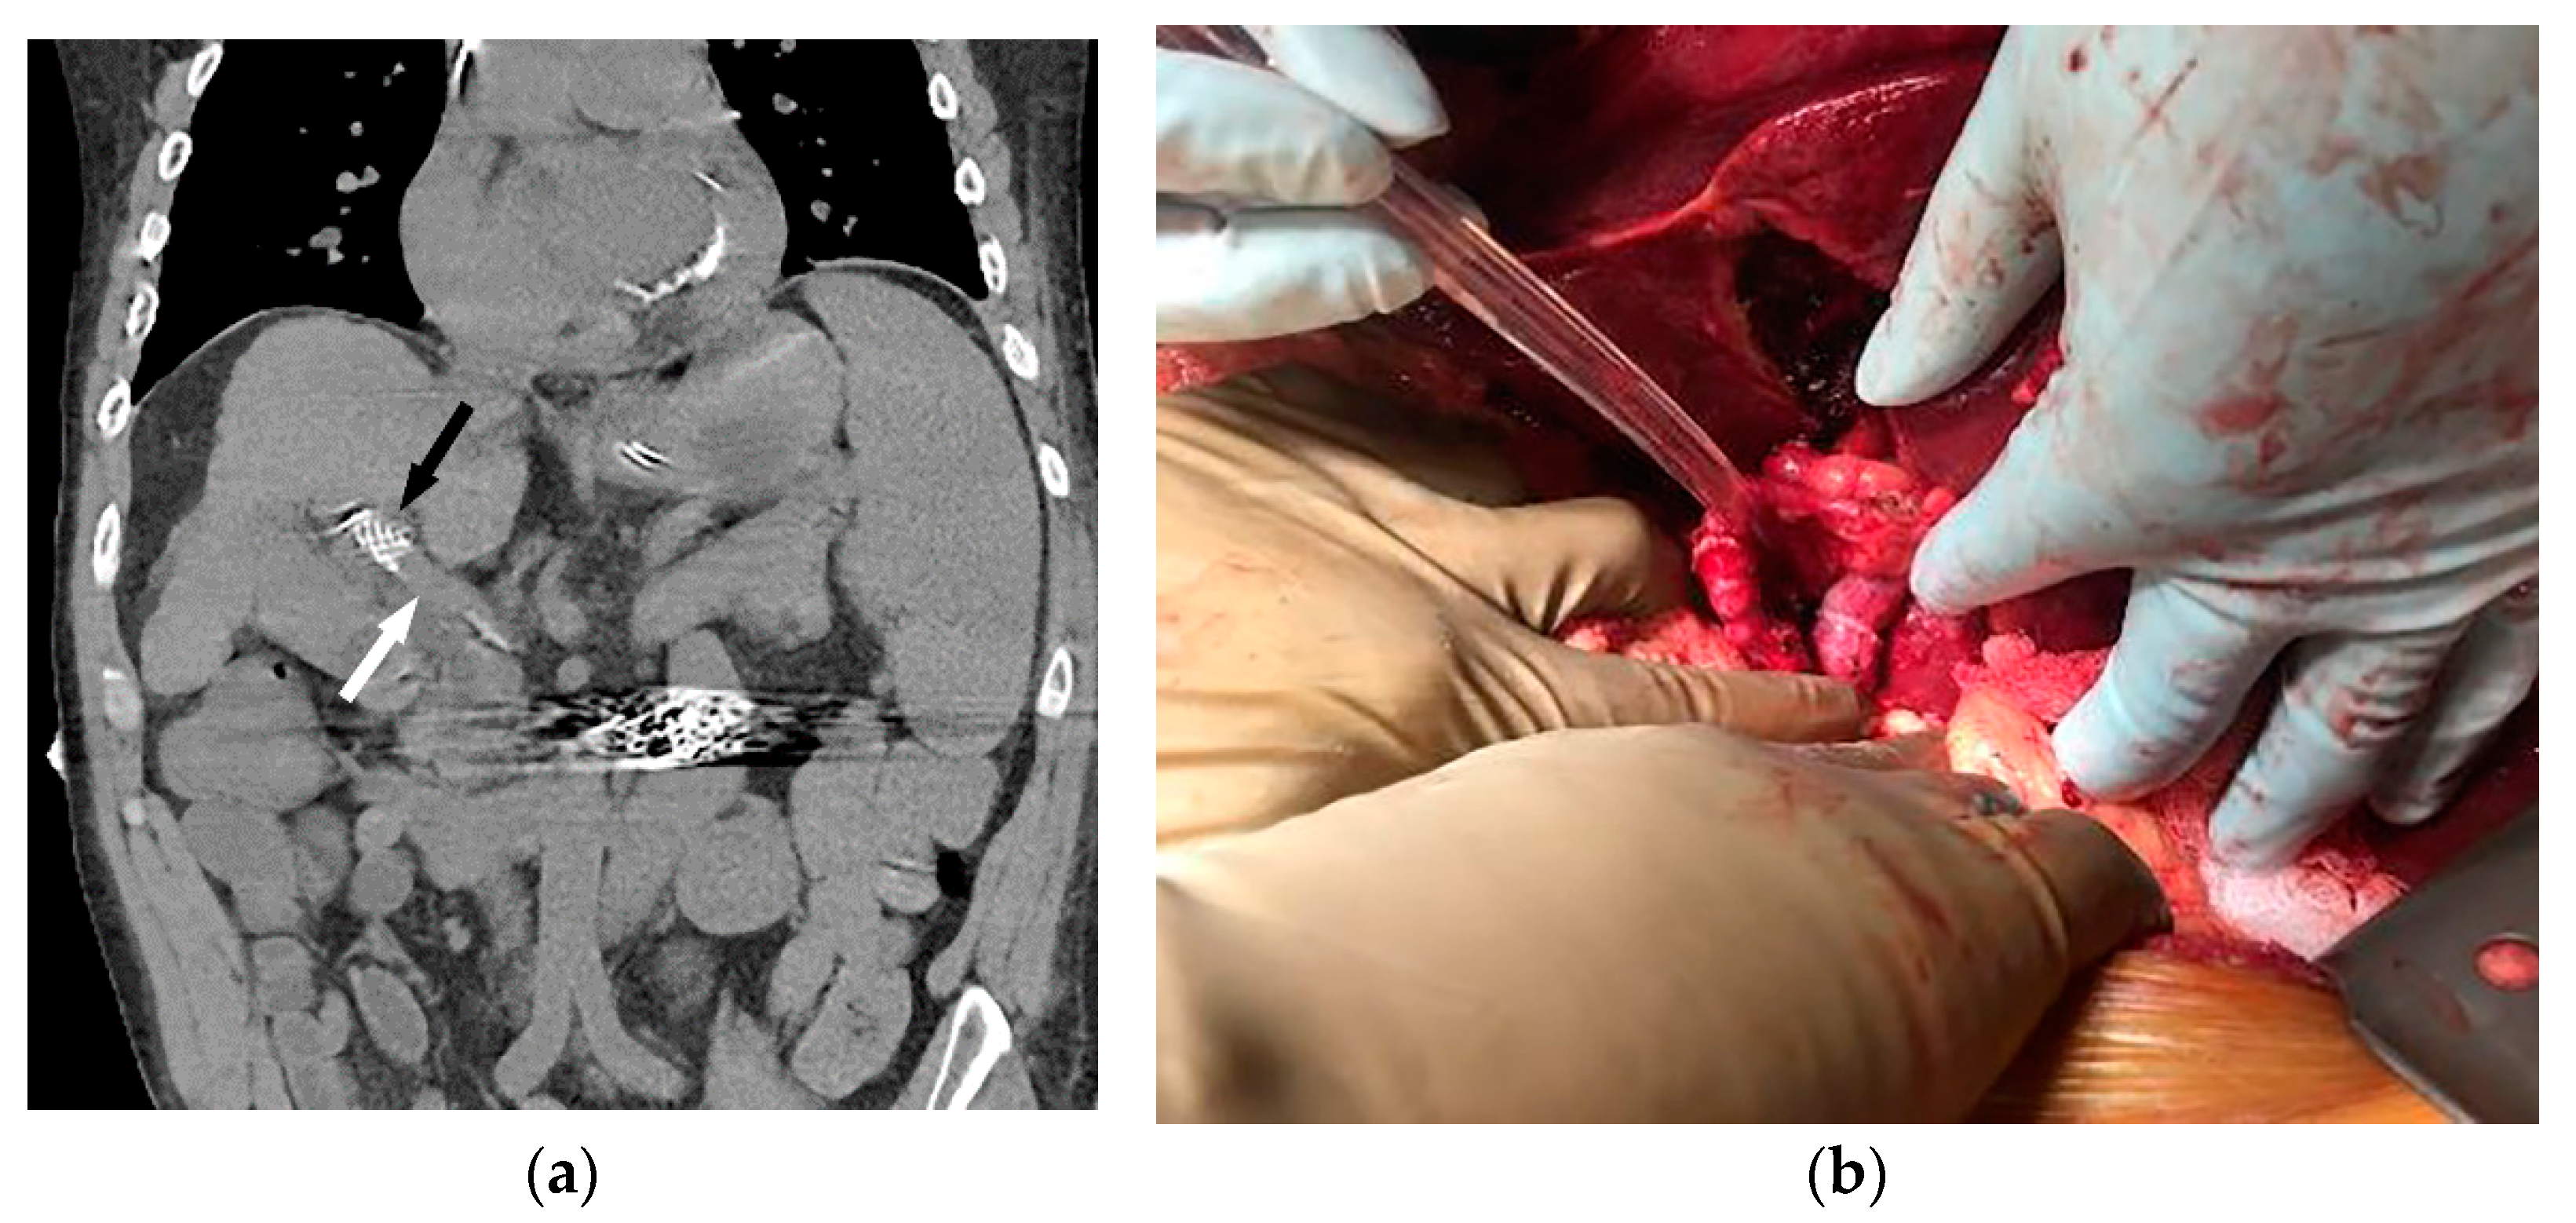

Figure 1.

56-year-old male with history of alcohol-related cirrhosis and portopulmonary syndrome. His baseline values included MELD-Na 19 (Tbili 4.0, INR 2.0, Cr 1.0, Na 137). He had imaging evidence of non-occlusive main portal vein thrombosis. Axial (a) and coronal (b) contrast-enhanced CT shows a diminutive portal vein (arrow). Coronal contrast-enhanced CT (c,d) demonstrates this extended to the portal venous confluence (arrow), with partially visualized component of a large inferior mesenteric vein to gonadal vein portosystemic shunt (S), which drained via the renal vein (arrowhead) to the inferior vena cava (*).